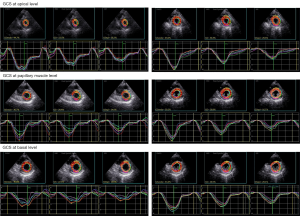

2D STE assessment

Two-dimensional STE was performed using a GE VIVID E95 ultrasound system. Images of the apical four-chamber, apical two-chamber, apical LV long-axis, and LV short-axis views at the basal, papillary, and apical levels were collected within 3–5 cardiac cycles. The software package EchoPAC (version 201 6.3, GE Vingmed Ultrasound) was used to analyze images. Software tracked the endocardium outline and divided the whole ventricle wall into three layers (an endocardial, a mid-myocardial and an epicardial layer). Quantitative myocardial parameters for the global longitudinal strain (GLS) and global circumference strain (GCS) of each layer, and PSD, were obtained. STE data analyses were conducted by two investigators (TL and ZW) who had experience with layer-specific STE and were blind to the clinical data.

The representative images of layer-specific STE’s of one SLE patient and one healthy control are shown in Figures 1 and 2 respectively, and the results of layer-specific STE parameters are displayed in Table 3. Although clinical evidence of cardiac involvement was not detected in SLE patients through routine assessment, an increase in impairment of left ventricular GLS at three layers (whole layer GLS, endocardial GLS, and epicardial GLS) was observed in drug-naïve patients with new-onset SLE, compared with controls (P=0.02, 0.01, 0.04, respectively). Elevation of PSD, which reflects left ventricular dyssynchrony, was also found in SLE patients (P<0.01). In contrast, there was no significant difference in the GCS of the three layers (midmyocardium GCS, endocardium GCS and epicardium GCS) at the basal, papillary, and apical levels between SLE patients and controls (P>0.05, all).